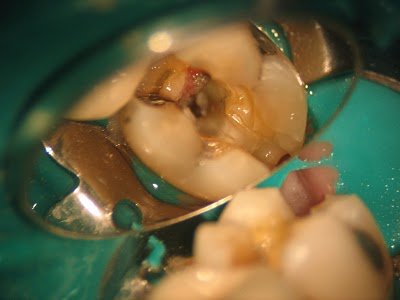

RCT initiated. Upon access, we find vital pulp tissue in the mesial canals, and necrotic pulp tissue in the distal canal.

Further removal of the distal crack finds the crack extending down the distal root, below the CEJ. Extraction is recommended.

However, things are not always a cut an dry as that. This case illustrates that “partially necrotic” pulp is a possible classification of pulpal status.